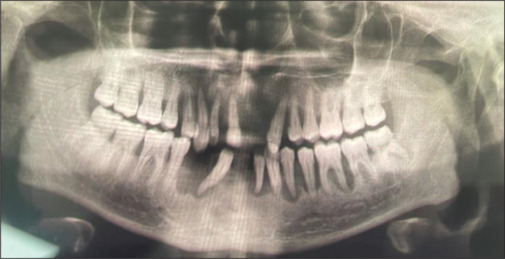

Langerhans cell histiocytosis (LCH) is a rare hematologic disorder characterized by the abnormal proliferation of Langerhans cells, resulting in a wide range of clinical manifestations and diagnostic challenges. A 36-year-old male presented with complaints of mobile teeth, gingival pain, and eczematous rashes on the toes. Clinical examination revealed advanced gingivitis, significant alveolar bone loss, and micronodular opacities in the chest on radiographic imaging. Histopathological and immunohistochemical analyses confirmed the diagnosis of LCH. This case underscores the diverse clinical spectrum of LCH and highlights the pivotal role of histopathology and immunohistochemistry in achieving a definitive diagnosis. Management strategies vary depending on the extent of disease involvement and may include surgical excision, corticosteroid therapy, or systemic chemotherapy. The case emphasizes the necessity of comprehensive evaluation and interdisciplinary collaboration in the diagnosis and treatment of rare disorders such as LCH.